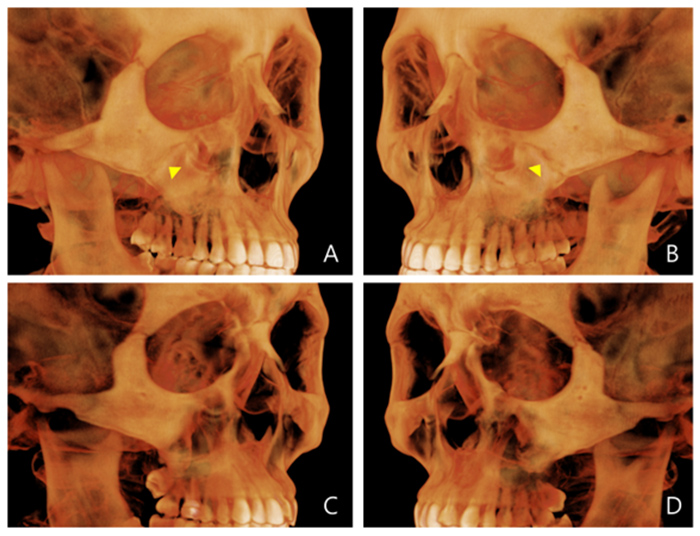

Evaluation of miniscrew-assisted rapid palatal expansion success by comparing width of circummaxillary sutures before expansion in adult male patients” – Angle Orthodontics

논문 발췌 사진

이지민 원장은 성인 비발치 교정의 핵심인 비수술 악궁 확장 가능성을, 직접 연구한 논문 결과를 바탕으로 사전에 정밀 분석·예측합니다.

이 연구들은 현재 연세꿈꾸는치과의

교정 프로토콜에 적용되고 있습니다.